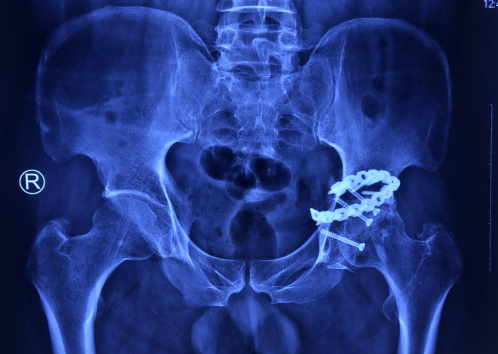

术前

因张先生坐骨神经损伤部位特殊,结合张先生有髋臼骨折内固定病史,明确了手术治疗方案,并对手术中可能出现的各种情况进行风险评估及制定应对处理措施,确定了手术时间。

陈主任组织医疗团队如期为张先生进行手术治疗,手术中发现,髋臼骨折部位一“游离骨块”卡压坐骨神经近端,分析患者左侧坐骨神经损伤长期不恢复主要原因为“游离骨块”卡压神经。手术中,将“游离骨块”仔细剥离、摘除,因局部瘢痕增生严重,坐骨神经高位损伤接近盆腔,操作中要注意保护臀下动脉,因此操作风险高,一旦动脉破裂会出现大出血、危及生命可能。“游离骨块”完整取除后,彻底松解神经周围瘢痕,神经松解后再次行术中肌电图检验神经恢复情况,术中肌电图检查提示神经松解后较手术前波幅升高,手术松解神经效果良好,手术顺利。手术后由拾啸康复医师对患者进行快速康复治疗。